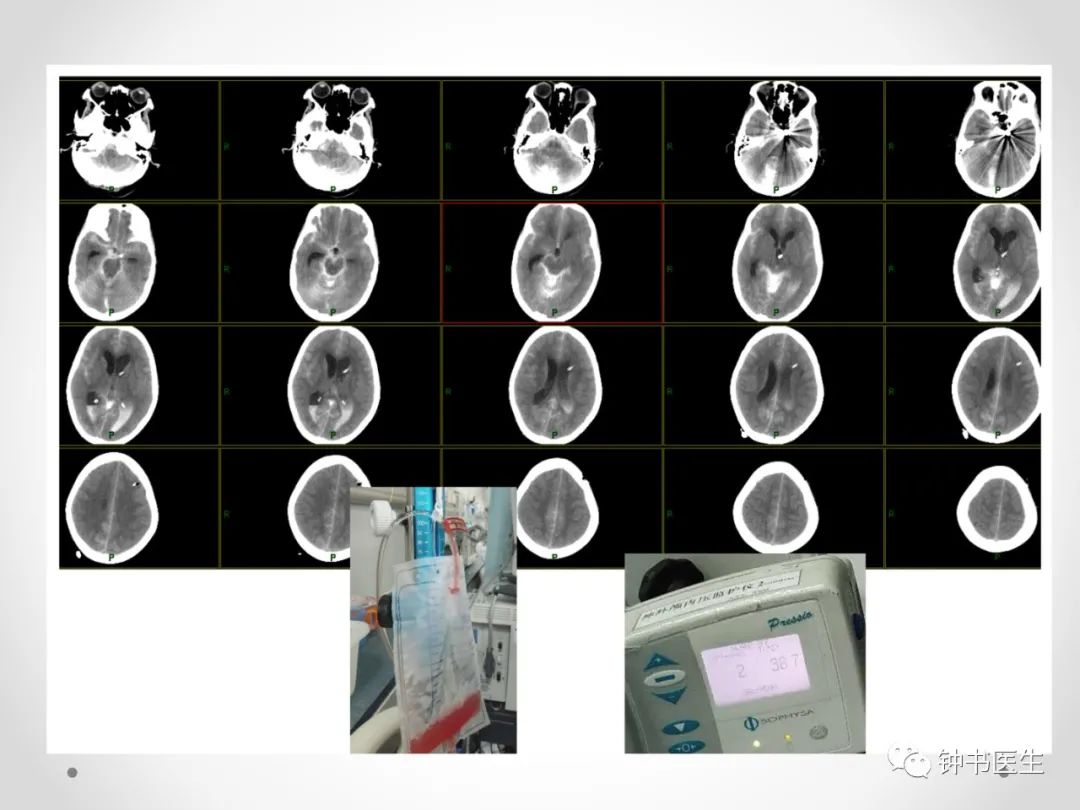

影响因素

测量误差;

微导管稳定性;

动脉瘤不规则形态;

弹簧圈特性;

术者经验。